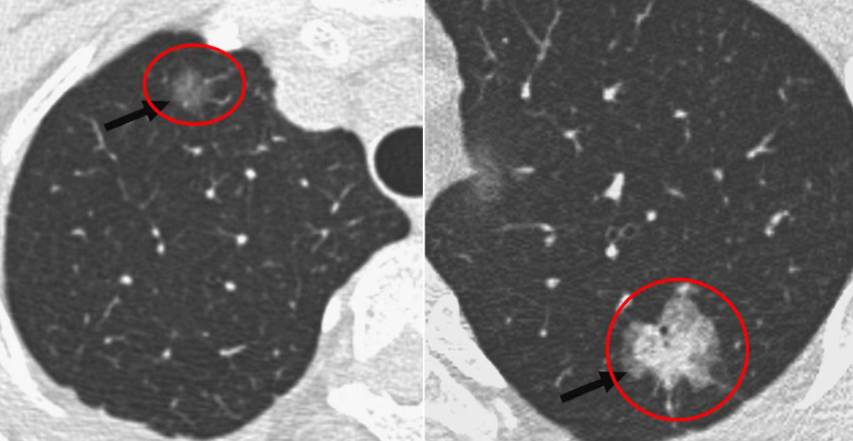

2、按结节密度分类

分为实性肺结节和亚实性肺结节。亚实性肺结节又包含磨玻璃病灶内不含有实性成分的纯磨玻璃结节(pGGN ,又称非实性结节),以及磨玻璃病灶内含有实性成分的混杂磨玻璃结节(mGGN ,又称部分实性结节)。